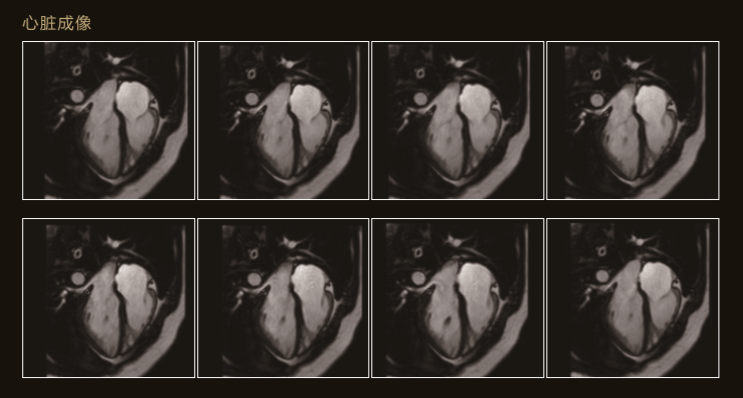

Apsaras飛天不僅采用極高均勻度的磁體系統,還配備了高階勻場系統可大範圍的高階磁場校正,以獲得具有臨床價值的圖像。

Apsaras飛天在保持以往使用便捷的前提下,應用程序支持更全面的臨床應用和發展。